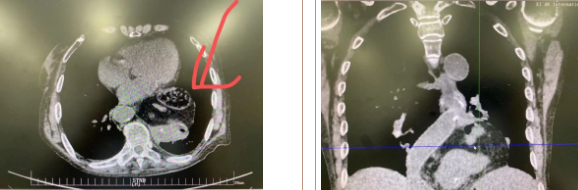

據(jù)了解,患者多年來進(jìn)食后出現(xiàn)惡心、嘔吐,卻未到醫(yī)院進(jìn)行檢查。3個月前患者突然出現(xiàn)無尿,全身腫脹等情況才前往就醫(yī),卻遭多家醫(yī)院拒收,輾轉(zhuǎn)來到我院就診。檢查發(fā)現(xiàn)患者已患宮頸癌、進(jìn)而引起腎后性腎衰、同時合并膈疝、出現(xiàn)泌尿道感染,病情及其復(fù)雜。

麻醉手術(shù)中心副主任丁倩為減輕患者術(shù)后不適,實(shí)施單腔聯(lián)合支氣管封堵插管,同時進(jìn)行了肋間神經(jīng)阻滯麻醉。術(shù)中發(fā)現(xiàn)患者膈疝巨大,食管和疝囊分界不清,部分胃組織和結(jié)腸疝已進(jìn)入胸腔。李文海憑借豐富的臨床經(jīng)驗(yàn),仔細(xì)辨別解剖變異,有序完成分離、縫合、修補(bǔ)等一系列操作,胸外科穆強(qiáng)副主任醫(yī)師、劉歡住院醫(yī)師、麻醉手術(shù)中心團(tuán)隊(duì)通力配合,手術(shù)最終順利完成,患者安全返回胸外科監(jiān)護(hù)室病房。目前患者術(shù)后恢復(fù)良好,于近日準(zhǔn)備出院。